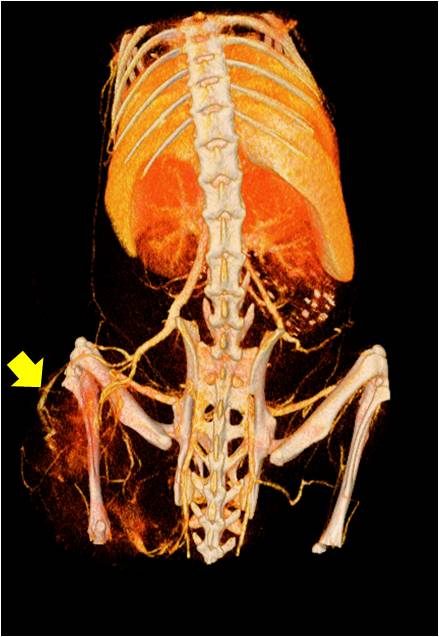

腫瘤血管生成

無造影劑注入 造影劑注入

心血管

胸部和心血管的層析成像 胸部和心血管的3D圖像